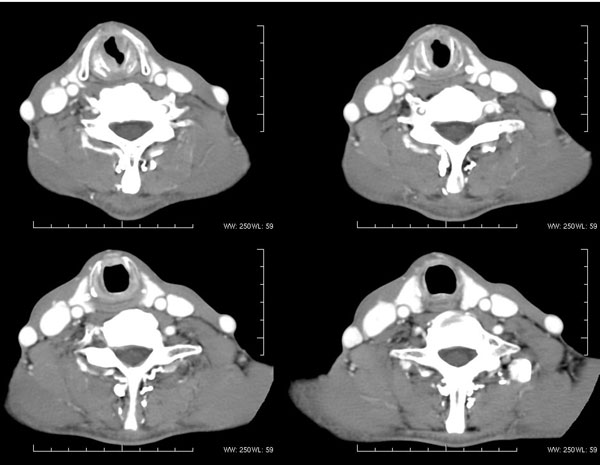

| 男性,57岁。反复声嘶1年,加重半年。 体检:喉粘膜充血,会厌肿胀,上举差,喉室及双声带窥视欠清。              蚂蚁发言:考虑喉癌(声门型)?双侧颈鞘周围淋巴结转移? 徐飞发言:有无呛水?根据病史要考虑球麻痹,脑干应检查 弯三角发言:考虑喉结核,应检查其它部位有无结核 卜一发言:喉腔右侧壁弥漫性软组织增厚,喉腔变窄。支持:喉癌(声门型)!另:双侧颈部多枚淋巴结肿大! 结果: 支纤镜检查:会厌板肿胀,右会厌咽侧壁肿胀,右杓状小结见结节样肿物,喉室肿胀,双声带肿胀、充血,左声带见菜花样肿物,触及易出血,取活检。 病理诊断:高分化鳞状细胞癌。 免疫组化:ck(h)(+++)、pcna(++)、p53(++)、ck(l)(-)。 原贴地址:http://www.radinet.com.cn/forum_view.asp?forum_id=4&view_id=34703 |